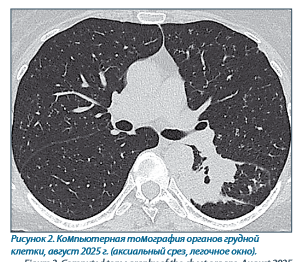

На контрольной серии КТ ОГК от августа 2025 года по сравнению с представленным исследованием от 30.01.25: в верхне-передне-медиальных отделах S6 левого легкого сохраняется образование неправильной формы с неровными, четкими, бугристыми контурами, с субсегментарными разветвлениями В6 в толще. Размеры образования - без убедительной динамики (50x30 мм), в структуре образования отмечается формирование единичных воздушных полостей диаметром до 5 мм. По сравнению с исследованием КТ ОГК от 30.01.25 - формирование распространенного респираторного бронхиолита с преобладанием изменений в верхних долях; формирование полостей распада в образовании S6 левого легкого; увеличение размеров аксиллярных лимфатических узлов (рисунок 2).